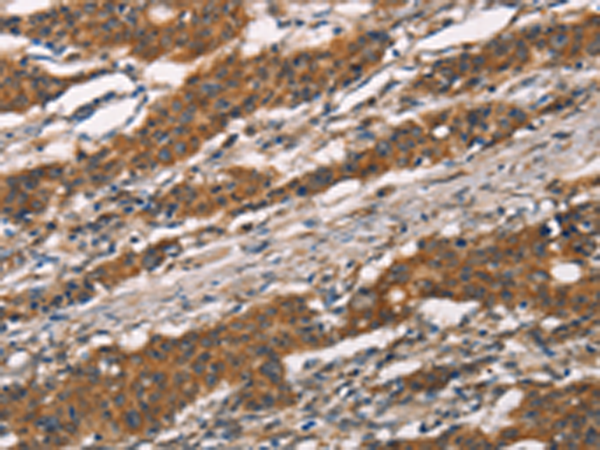

ELISA, IHC |

IHC positive control: |

Human gastric cancer and human thyroid cancer |

IHC Recommend dilution: |

25-100 |